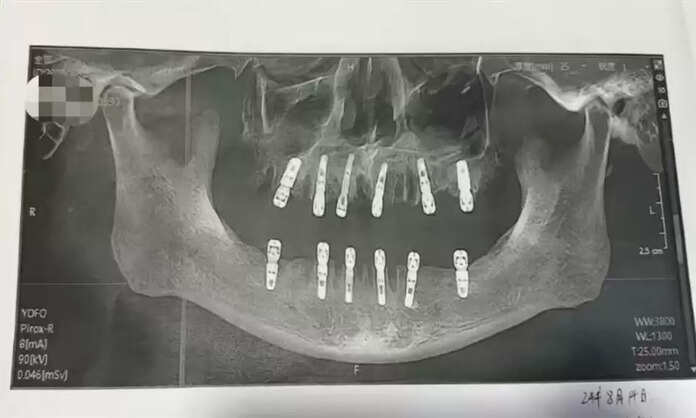

அறுவை சிகிச்சையின்போது அவரின் 23 பற்களும் பிடுங்கப்பட்டு அதே நாளில் 12 புதிய பற்கள் இம்மீடியேட் ரெஸ்டோரேஷன் [Immediate restoration] முறை இம்பிளாட் செய்யப்பட்டுள்ளது.